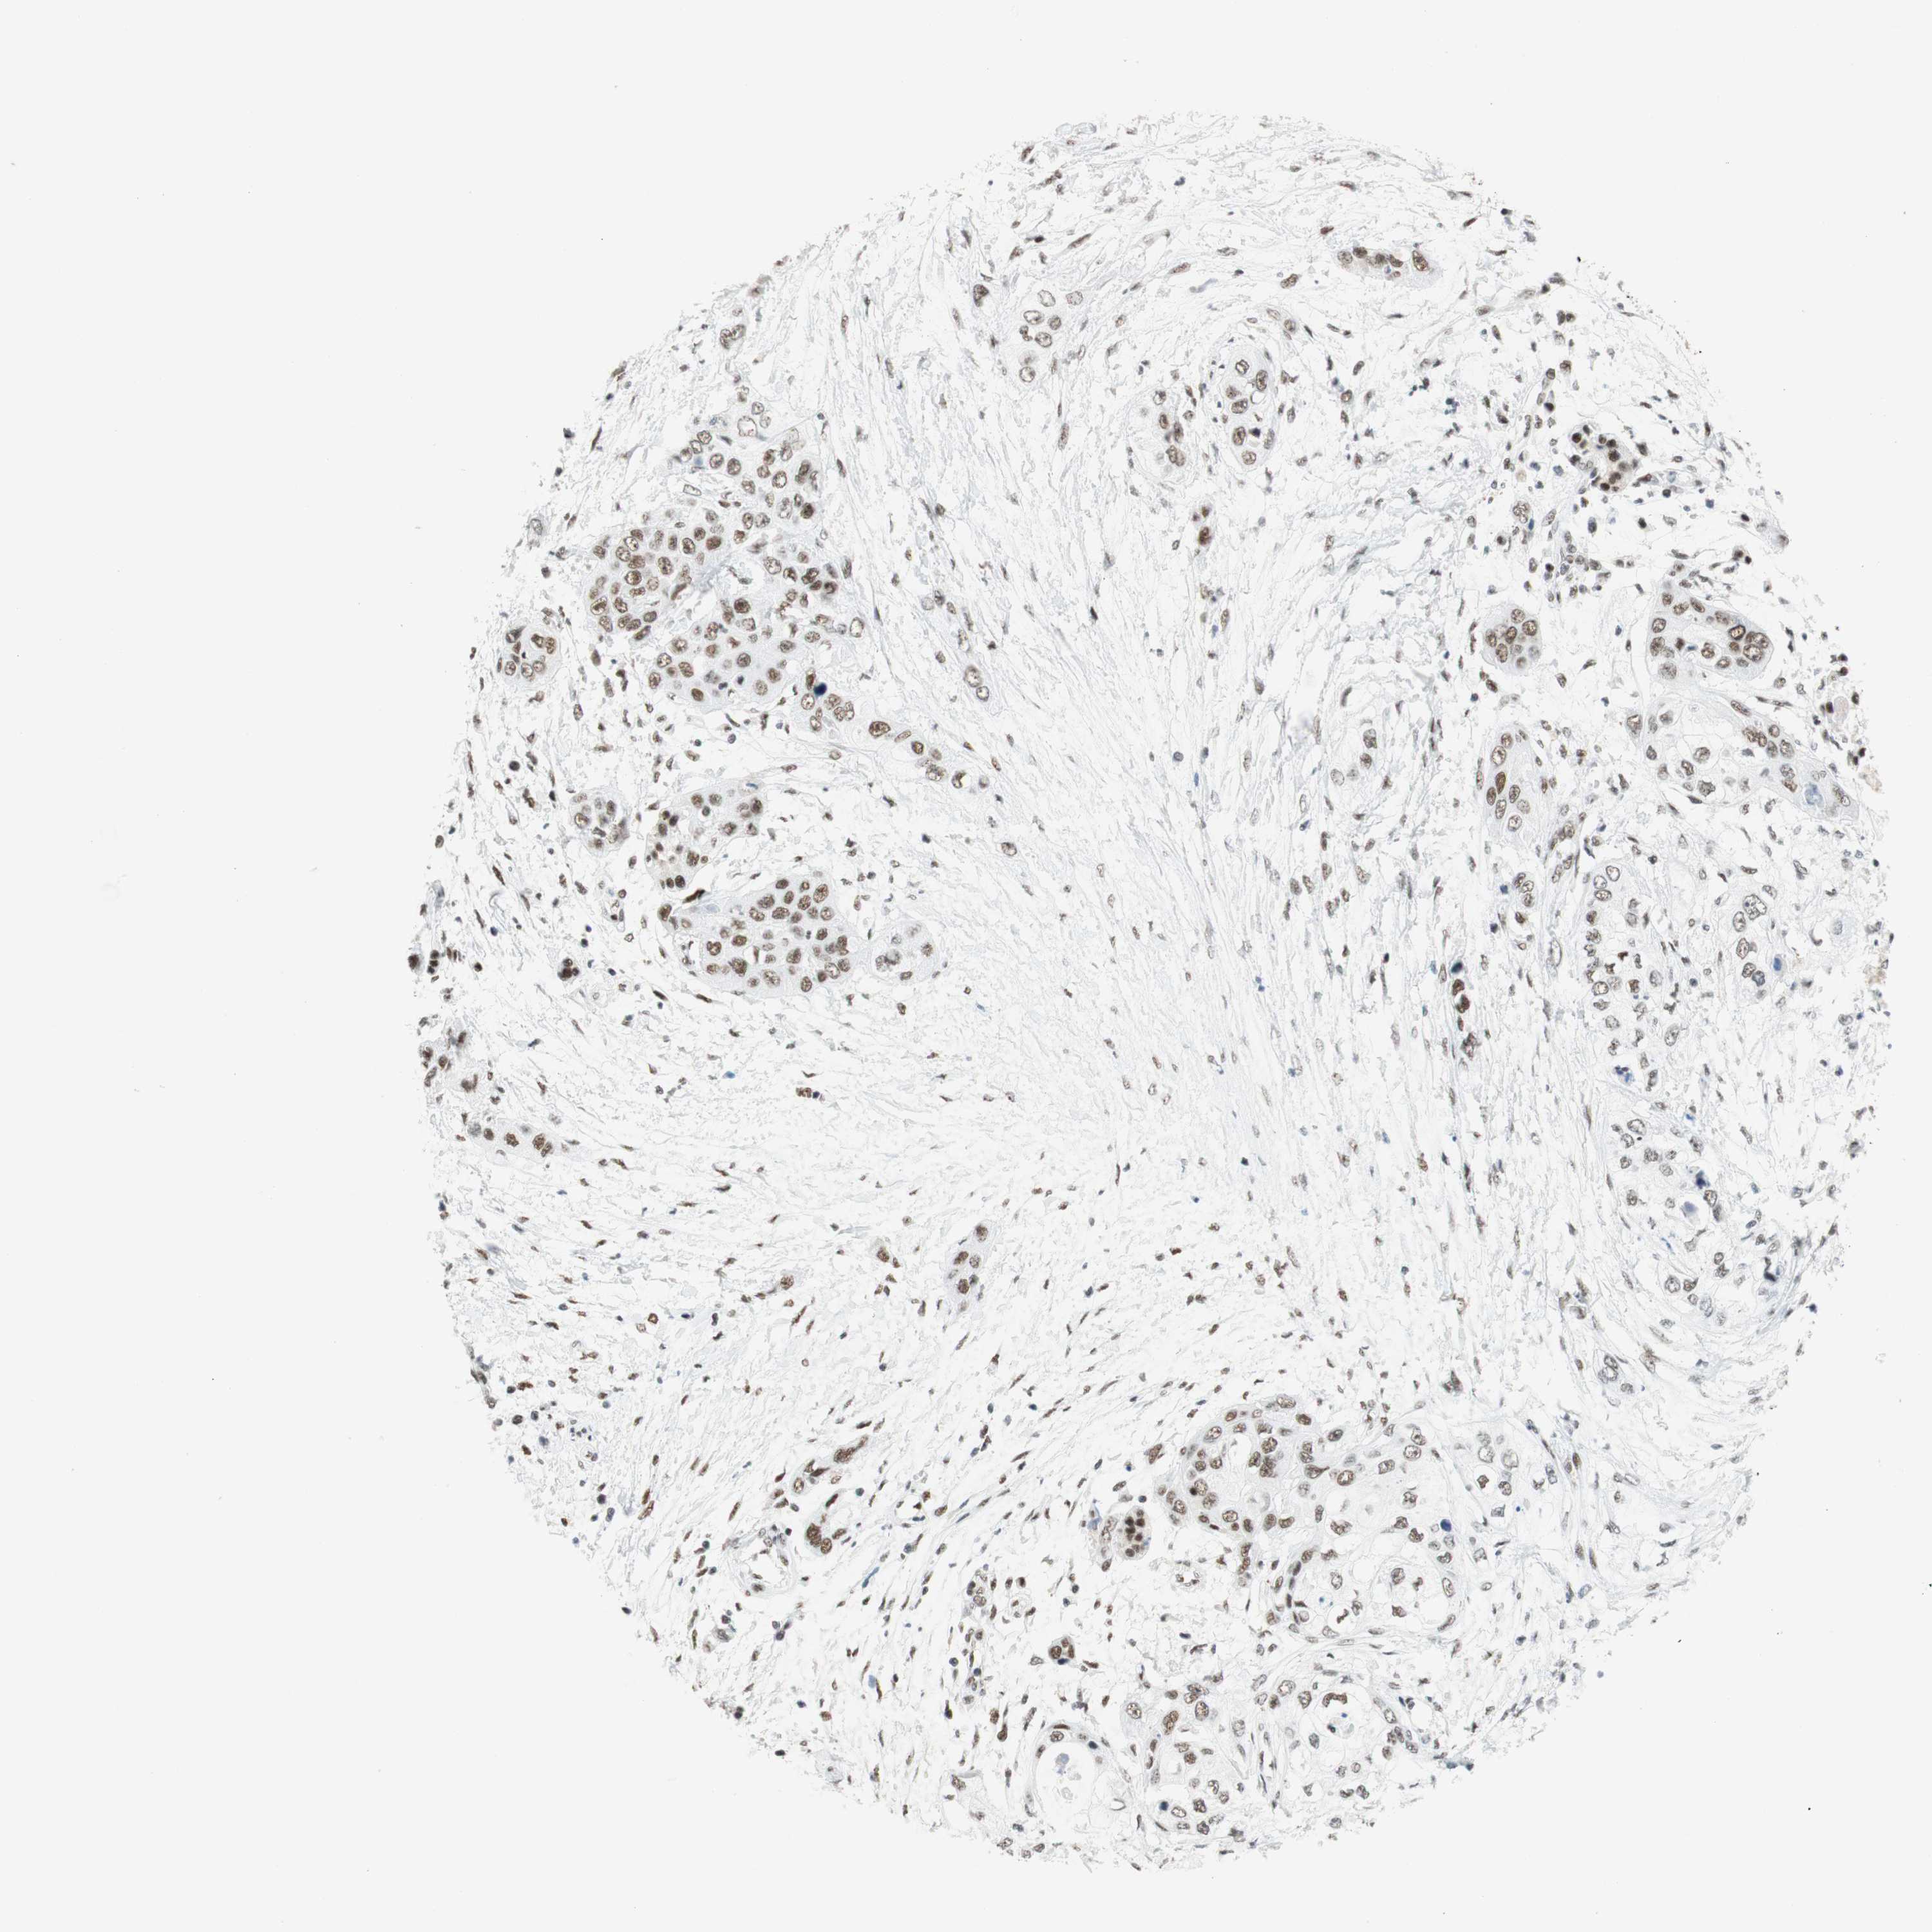

PANCREATIC CANCER - Protein expressioni

A mouse-over function shows sample information and annotation data. Click on an image to view it in a full screen mode. Samples can be filtered based on level of antibody staining by selecting one or several of the following categories: high, medium, low and not detected. The assay and annotation is described here.

Note that samples used for immunohistochemistry by the Human Protein Atlas do not correspond to samples in the TCGA dataset.

Antibody stainingi

Antibody staining in the annotated cell types in the current human tissue is reported as not detected, low, medium, or high, based on conventional immunohistochemistry profiling in selected tissues. This score is based on the combination of the staining intensity and fraction of stained cells.

Each image is clickable and will lead to virtual microscopy that enables deeper exploration of all samples and also displays staining intensity scores, fraction scores and subcellular localization as well as patient and tissue information for each sample.

Antibody CAB012478

Adenocarcinoma, NOS

Adenocarcinoma, metastatic, NOS